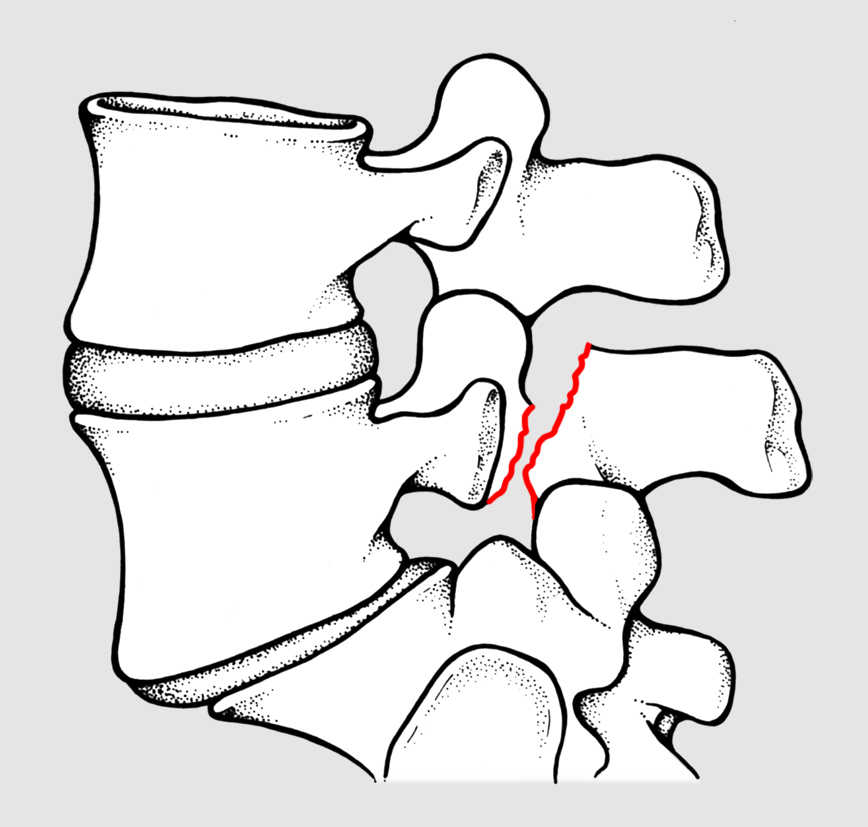

Per spondilolisi si intende l’interruzione di quella parte dell’arco posteriore vertebrale compresa fra le due apofisi articolari (fig 1). Se bilaterale, essa può favorire lo scivolamento in avanti di una vertebra rispetto a quella sottostante, realizzando così la spondilolistesi (fig 2).

La lisi, spesso asintomatica, si localizza quasi sempre nel tratto lombare inferiore (in particolare IV e V vertebra lombare) ed è più frequente di quanto si creda, realizzandosi per il concorrere di fattori ereditari congeniti (displasia dell’istmo) o meccanici (microtraumi in iperestensione in soggetti con iperlordosi lombare). Il viraggio sintomatologico (lombalgia) si verifica in età scolare o più spesso adolescenziale. La diagnosi è radiografica: oltre alle proiezioni antero-posteriore e latero-laterale, sono necessarie le proiezioni oblique che mostreranno l’immagine tipica del cagnolino con una interruzione (lisi) a livello del collo (fig 3). Una volta fatta la diagnosi, bisognerà consigliare le stesse norme comportamentali valide per l’iperlordosi lombare, senza precludere al bambino la possibilità di praticare attività sportive, ma sconsigliando quelle (come la ginnastica artistica, il judo, il salto in alto, il nuoto stile delfino, il surf, etc.) che comportano un forte lavoro in iperestensione del rachide lombare.